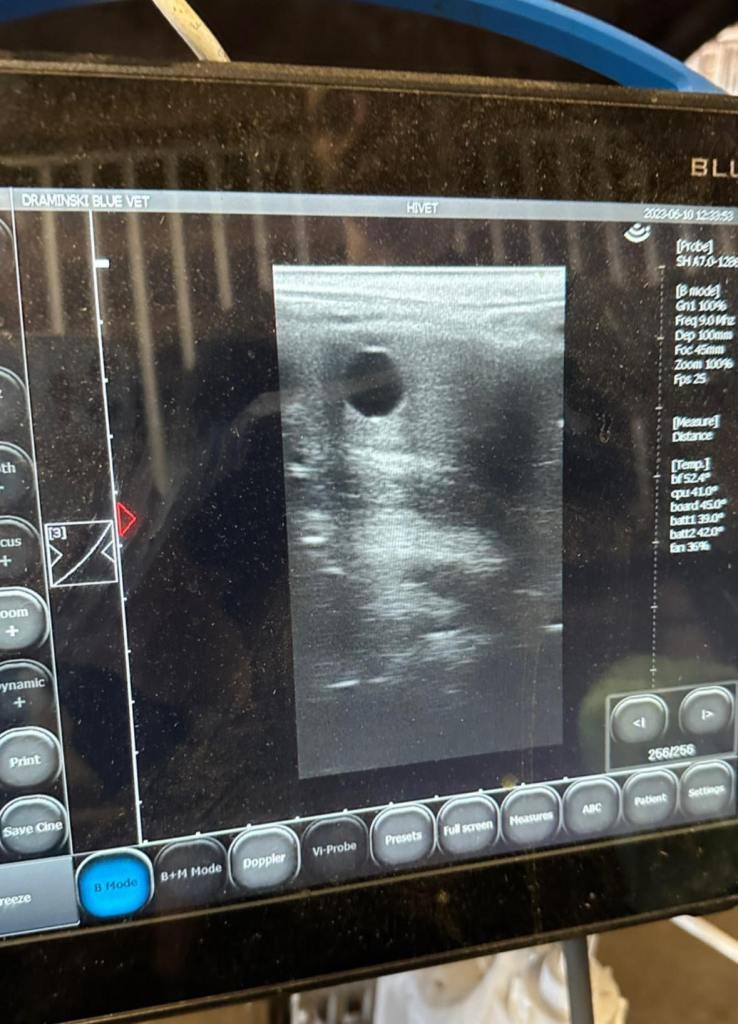

Juunis saime teate, et on oodata neljajalgset perelisa! Kahjuks jäi kolmest ratsahobuse märast tiineks vaid üks, kuid kogu see teekord on meie jaoks olnud hindamatu väärtusega – oleme väga palju õppinud ning järgmisele hooajale lähme palju targemana vastu. Alguses olime küll üsna õnnetud, kuid järelikult polnud ette nähtud ning uuel aastal uue hooga!